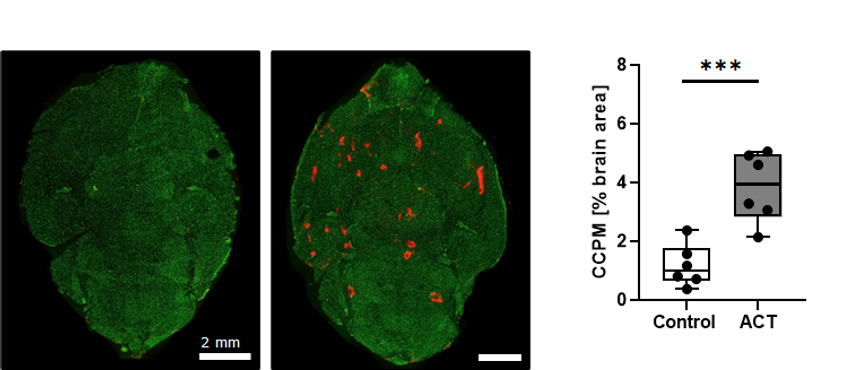

Forskere ved Insitutt for fysikk ved NTNU har i samarbeid med bedriften Exact Therapeutics tatt i bruk en helt ny type gassboble som er større enn gassboblene som er brukt tidligere. Denne teknikken kalles «Acoustic Cluster Therapy» eller ACT.

- På grunn av av størrelsen på mikroboblen legger den seg langs blodåreveggen i kapillærene i kontakt med mange av cellene som danner blod-hjernebarrieren. Et nytt sett av ultralydpulser får den store gassboblen til å vibrere og effektivt åpne blod-hjernebarrieren.

Samtidig kan vi injisere legemidler for eksempel kapslet inn i nanopartikler. Forskerne ved NTNU har vist at ved bruk av ACT kan slike nanopartikler passere blod-hjerne barrieren og komme frem til hjernevevet i mus.

– Metoden øker gjennomtrengeligheten over blod-hjernebarrieren. Den øker også opptaket av store molekyler og nanopartikler i hjernen, sier professor de Lange Davies. – I museforsøkene våre har vi vist at blod-hjernebarrieren lukker seg etter cirka et døgn, og vi finner ingen vesentlige skader på hjernevevet.